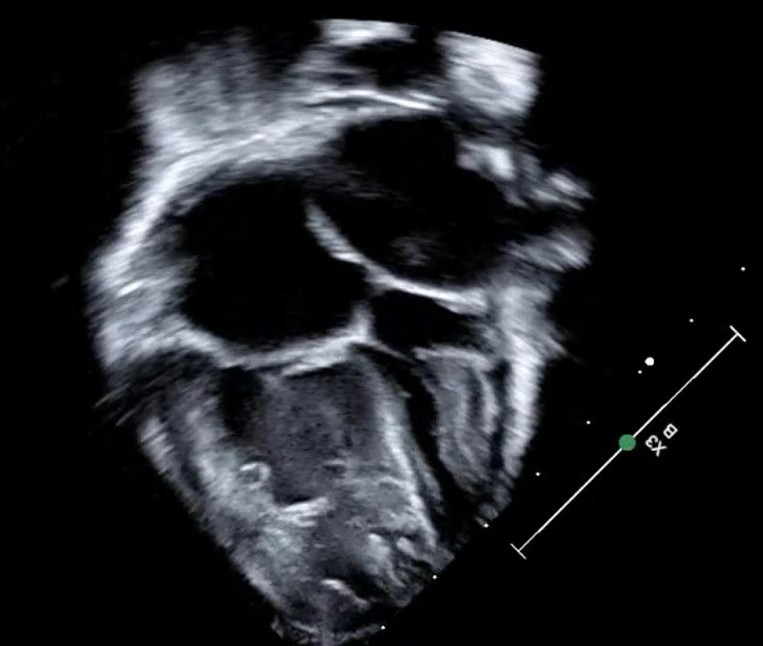

A 34-year-old G2P1 pregnant woman presents for prenatal ultrasound at 20 weeks of gestation, and the fetus is found to have congenital heart disease (CHD). The detection of which of the following lesions, when identified on fetal echocardiography, is MOST LIKELY to result in decreased mortality when compared to children with a postnatal diagnosis of the same lesion?

- A. Interrupted aortic arch (IAA)

- B. Complete Atrioventricular Canal (CAVC) defect

- C. D-Transposition of the Great Arteries (d-TGA)